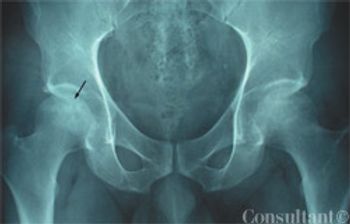

Pain in the right hip that had gradually worsened within the past month prompted a 42-year-old man to seek medical attention. The pain was aggravated by lifting the right leg and by walking; it was relieved by ibuprofen. The patient denied recent trauma, fever, overexertion, numbness, leg weakness, and back pain. He had had a discectomy for a herniated lumbar disk several years earlier. There was no history of sickle cell disease or allergies. He reported occasional alcohol use.